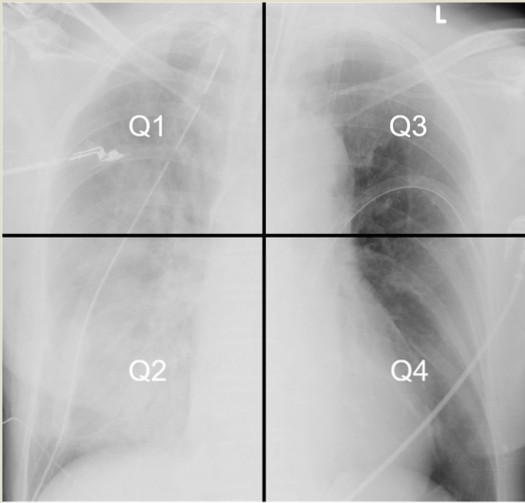

单侧毛细血管静水压明显升高。如缺血、创伤、穿孔等导致二尖瓣反流使得单侧或单支肺静脉压明显升高等[26-30](见图 1)。单侧或单支肺静脉受压、狭窄、堵塞、解剖变异、手术缝合、血栓形成、左心房肿物、硬化性纵膈炎等回流受阻导致同侧PE[31-36];一侧肺动脉阻力增加,如动脉瘤、主动脉夹层、扩大的左心室等压迫肺动脉[37, 33, 38],急性单侧肺栓塞、单侧大量气胸导致对侧血流快速增加诱发对侧PE[24, 39];支气管单侧堵塞发生患侧血管缺氧收缩诱发对侧UPE[40];长时间单侧卧位[41]。总之导致单肺血流增加的因素都可能诱发UPE。

| 图 1 UPE病因 |

UPE可根据诱因分为心源性UPE和非心源性UPE,心源性UPE主要由二尖瓣反流和左心衰导致,主要累及右侧(见图 1);而非心源性UPE诱因众多(见表 1)。